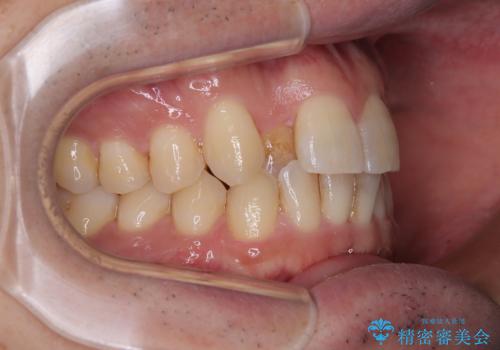

- 上下前歯のデコボコを気にして来院された患者様です。

ワイヤー矯正でもマウスピース矯正でも可能でしたが、短期間で、自身の手を煩わせることなく治療を行いたいとのことで、ワイヤー装置にて矯正治療を行うこととしました。

上顎前歯の舌側転位が顕著であったため、治療期間が長くなると思われましたが、僅か1年で無事に終えることができました。